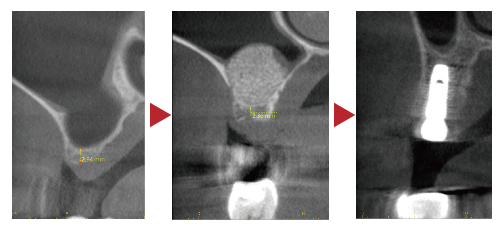

▲六個月後,顎骨的厚度與高度已足以支撐人工牙根,醫師便能順利完成植牙。

在這個階段,骨再生膜與支撐釘會一併移除,確保人工牙根能穩定植入並與新生骨組織緊密結合。【註3】